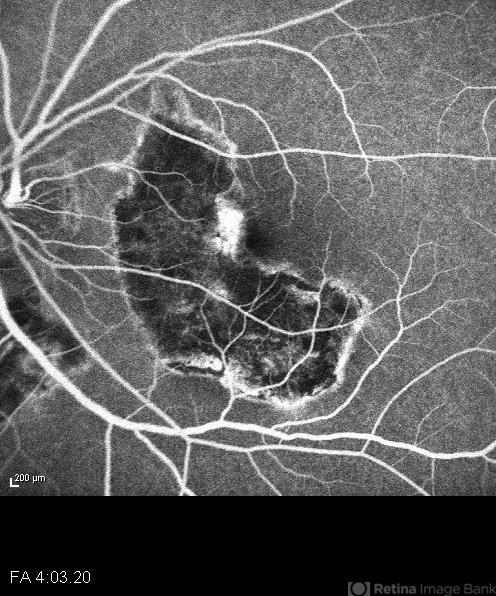

- macula serpiginous choroidopathy

- HRA

- 9/11/2012